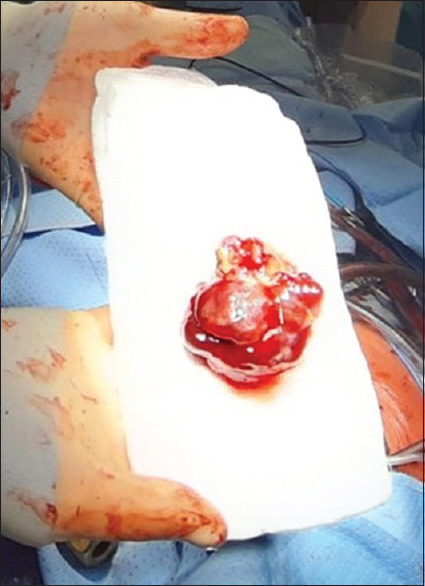

摘要:从右心室延伸出来的心脏肌瘤并不常见,这种罕见的情况可能与多种风险和不良预后有关。我们报告了一例右心室肌瘤患者的病例,该患者近期因动静脉畸形导致出血性中风。术前和术中的处理都极具挑战性,需要医疗团队做出若干艰难的选择,因此,必须采用多学科方法并进行效益风险评估,才能在紧急情况下及时决定手术切除,同时避免延误或不当治疗,在风险极高的情况下取得成功的结果。

Abstract: Cardiac myxomas extending from the right ventricle are uncommon and this rare condition is potentially associated with several risks and poor outcomes. We report the case of a patient with a right ventricular myxoma who had a recent haemorrhagic stroke due to an arteriovenous malformation. The preoperative and intraoperative managements were challenging and required several difficult choices by the medical team and consequently, a multidisciplinary approach and a benefit-risk evaluation were necessary to determinate timely surgical resection in an urgent situation, simultaneously avoiding delayed or improper treatments, achieving a successful outcome in a very high-risk situation.